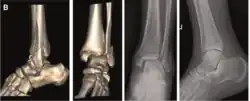

| Supination-External rotation |

|

![]() |